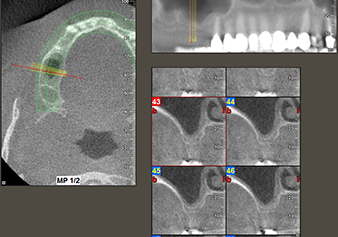

Una paziente di 49 anni, non fumatrice e con un'anamnesi priva di elementi rilevanti, è stata indirizzata al nostro studio di chirurgia orale per l'estrazione chirurgica del dente 16 ed il successivo impianto. Dopo l'estrazione, la paziente ha accusato dei lievi dolori causati dalla sinusite, motivo per cui abbiamo inizialmente aspettato sei mesi prima di procedere con l'intervento. L'altezza ossea residua in corrispondenza della posizione dell'impianto misurava 3-4 mm (Fig. 1 e 2).